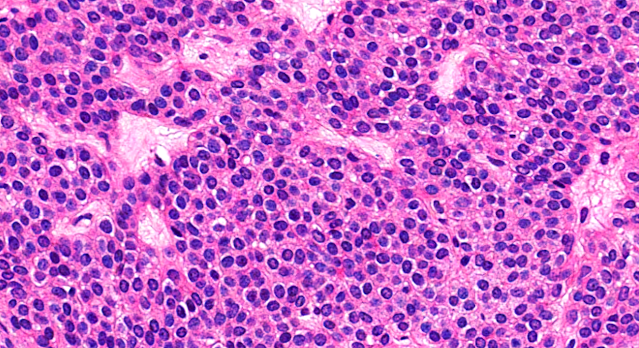

Dermatopathology Case 219 Get link Facebook X Pinterest Email Other Apps May 23, 2022 A 35 year old man with a nodule on the left middle finger. Answer Get link Facebook X Pinterest Email Other Apps Comments